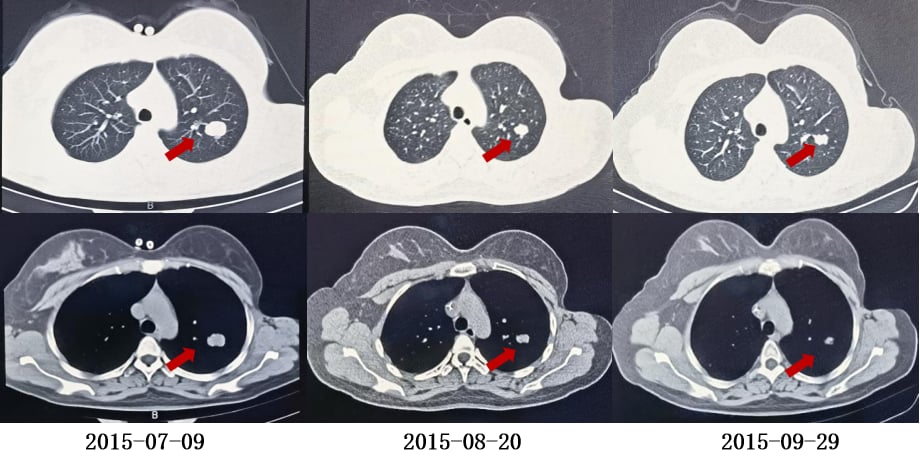

不幸的是,在无病生存24个月后,2015年7月,患者出现第一次复发,胸部CT显示右肺及左肺上叶、胸膜下多发软组织结节,考虑转移。头颅CT、骨扫描、腹部CT未见明显异常。BRCA基因检测未发现明确致病突变。

面对复发,患者接受了以下治疗:

- 解救化疗:GP方案(吉西他滨+顺铂)4周期,但因出现III-IV度骨髓抑制,调整为吉西他滨单药化疗2周期。

- 一线维持治疗:戈舍瑞林(卵巢功能抑制剂)+来曲唑(芳香化酶抑制剂)进行内分泌治疗,疗效评价为部分缓解(PR)。